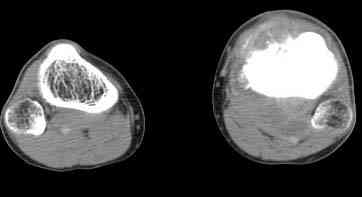

важаемые коллеги! Поступил больной 22 лет. Болен с января 2006 - появились боли в области верхнейтрети голени. При первичном осмотре в поликлинике был заподозрен первично-хронический остеомиелит - осмотрен гнойным хирургом - произведена биосия . Заключение - хондросаркома. Осмотрен онкологом - с учетом характера опухоли - химиотерапия, лучевое лечение не показано. Предложена либо ампутация, либо решение вопроса о возможности выполнения органосохраняющей операции. При обращении к нам произведена сцинтиграфия скелета - зоны гиперфиксации РФП: верхняя треть голени- 960%, нижняя треть бедра - 380%, Дистальный метафиз голени и затылочная область - 140%. В легких - метастазов нет. Произведена КТ (картинки в приложении). Учитывая абсолютную нестыковку рентгенологических и морфологических данных повторно биопсия. Выявлено, что первичная биопсия выполнялась из поверхностной параоссальной зоны - там локализованы хрящеподобные массы, далее очень плотная кость без хрящевых участков - биоптат взят фрезой с большим трудом. Морфологического заключения пока нет. Хотелось бы узнать Ваши варианты диагноза и соответственно тактику.

Не специалист по онко ортопедии, но по локализации (бедро, большеберцовая и плечевая кость), возрасть, в данный момент отсутствия метастаза и формация новой кости с мягкотканним вовлеченим, процесс больше напоминает остеосаркому большеберцовой кости.

Припухлость над опухолью и кожные изменения, подобно воспалительной и боли при нагрузке могут быть приняты общими ортопедами как остеомиелитический процесс.